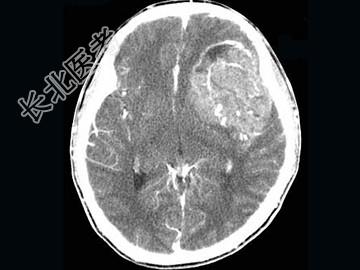

- 单项选择题男,15岁, 进行性头痛1年余,CT检查, 最可能的诊断为 ( )

A、脑膜瘤

B、脑血管畸形

C、转移瘤

D、淋巴瘤

E、胶质母细胞瘤